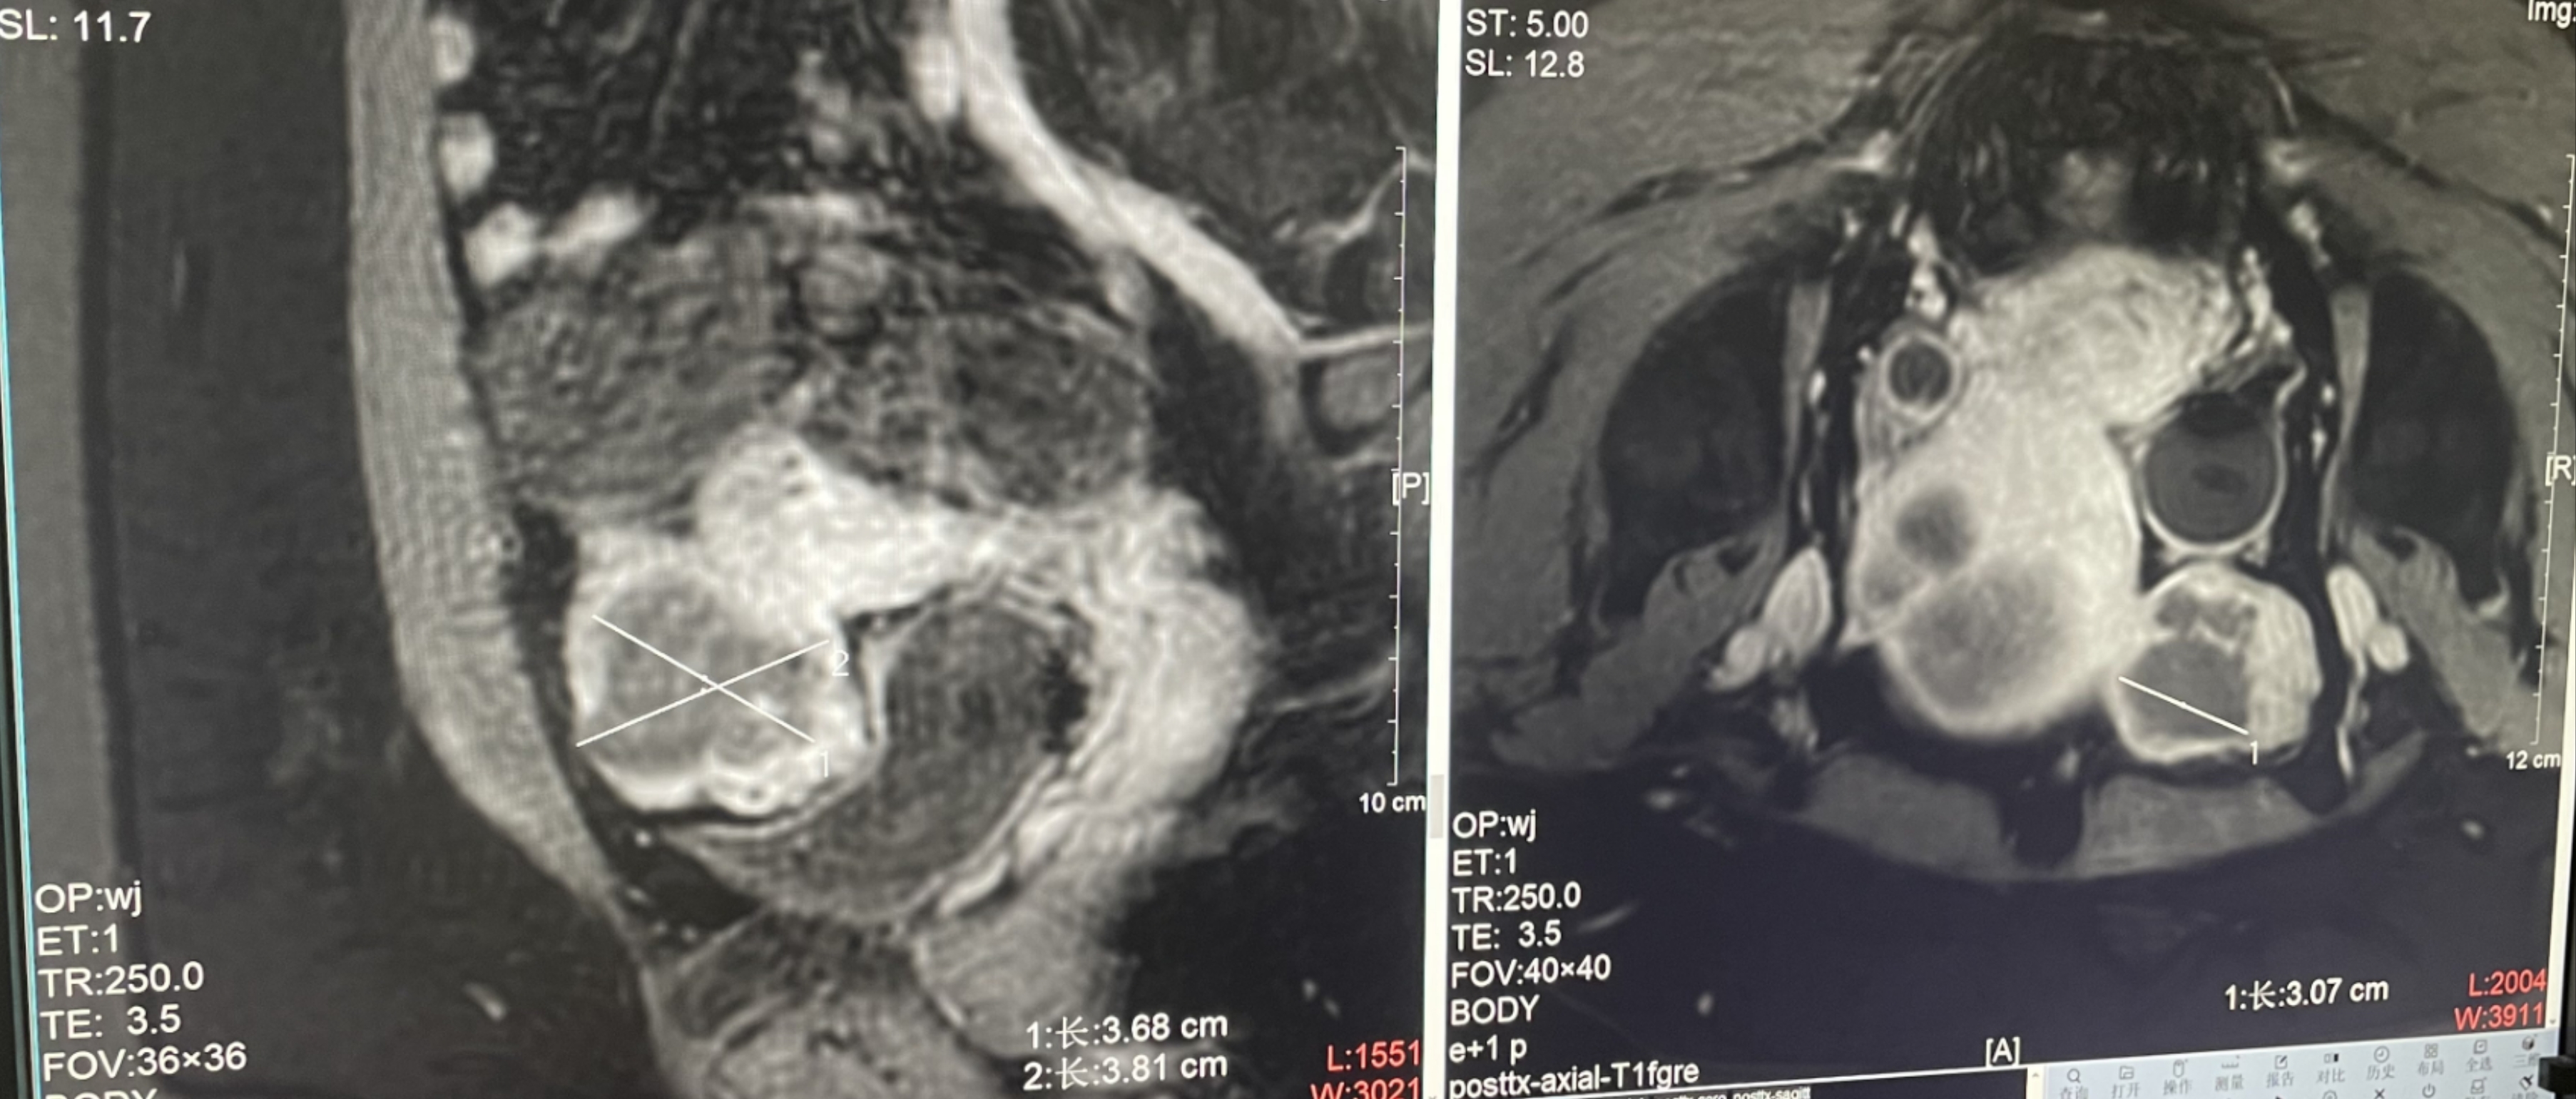

診斷:子宮肌瘤

腫瘤尺寸:約為45*52*38mm

ROT深度:腫瘤的ROT中心距離皮膚62mm

術后評估:術后造影增強圖像顯示消融區(qū)域(右側)與腫瘤區(qū)域(左側)重合度較好,非灌注區(qū)域連續(xù)且一致。

結論:對該腫瘤具有非常好的消融效果,治療過程中,溫度上升曲線符合預期,每個被治療的靶點240CEM區(qū)域體積較大、外形飽滿、連續(xù)。病灶消融良好,NPV體積比約88.7%。